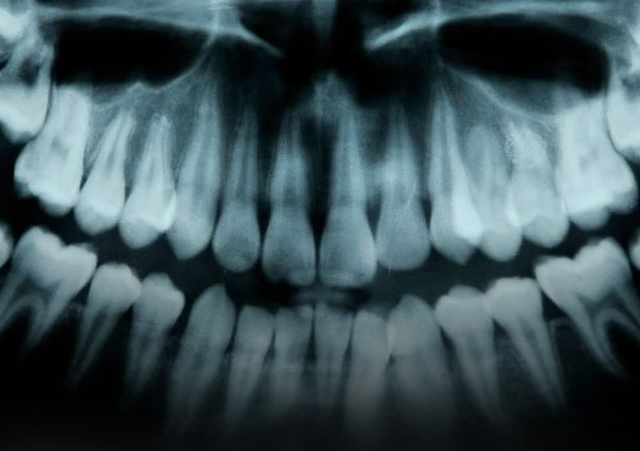

Снимок зубов